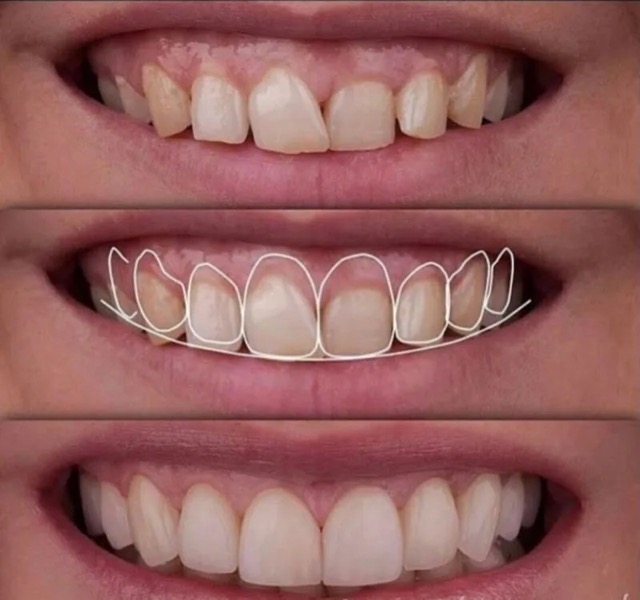

Patient presented to the office with a concern about spaces between the teeth and slight discoloration. A detailed smile analysis with initial pictures, x rays, a scan of the teeth was used to fabricate a mock up smile.

Temporary veneers were fabricated that were given to the patient to test for a week before finally fabricating permanent porcelain veneers to give the teeth a vital, youthful and a natural look.